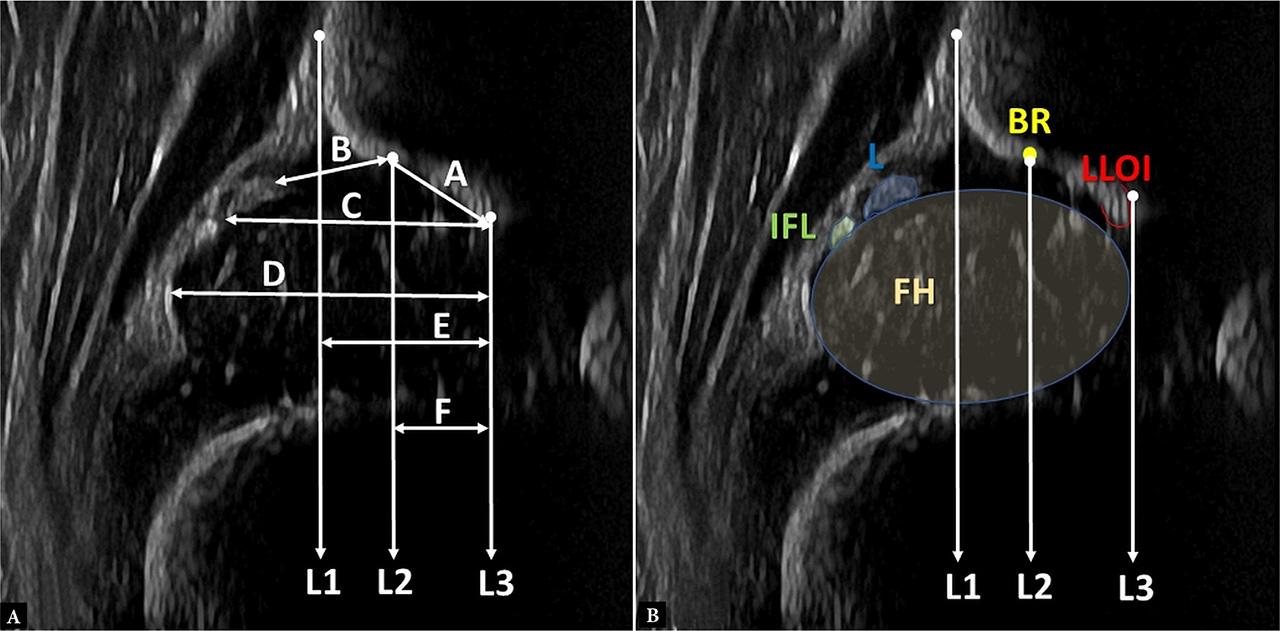

Fig. 1.

Fig. 2.